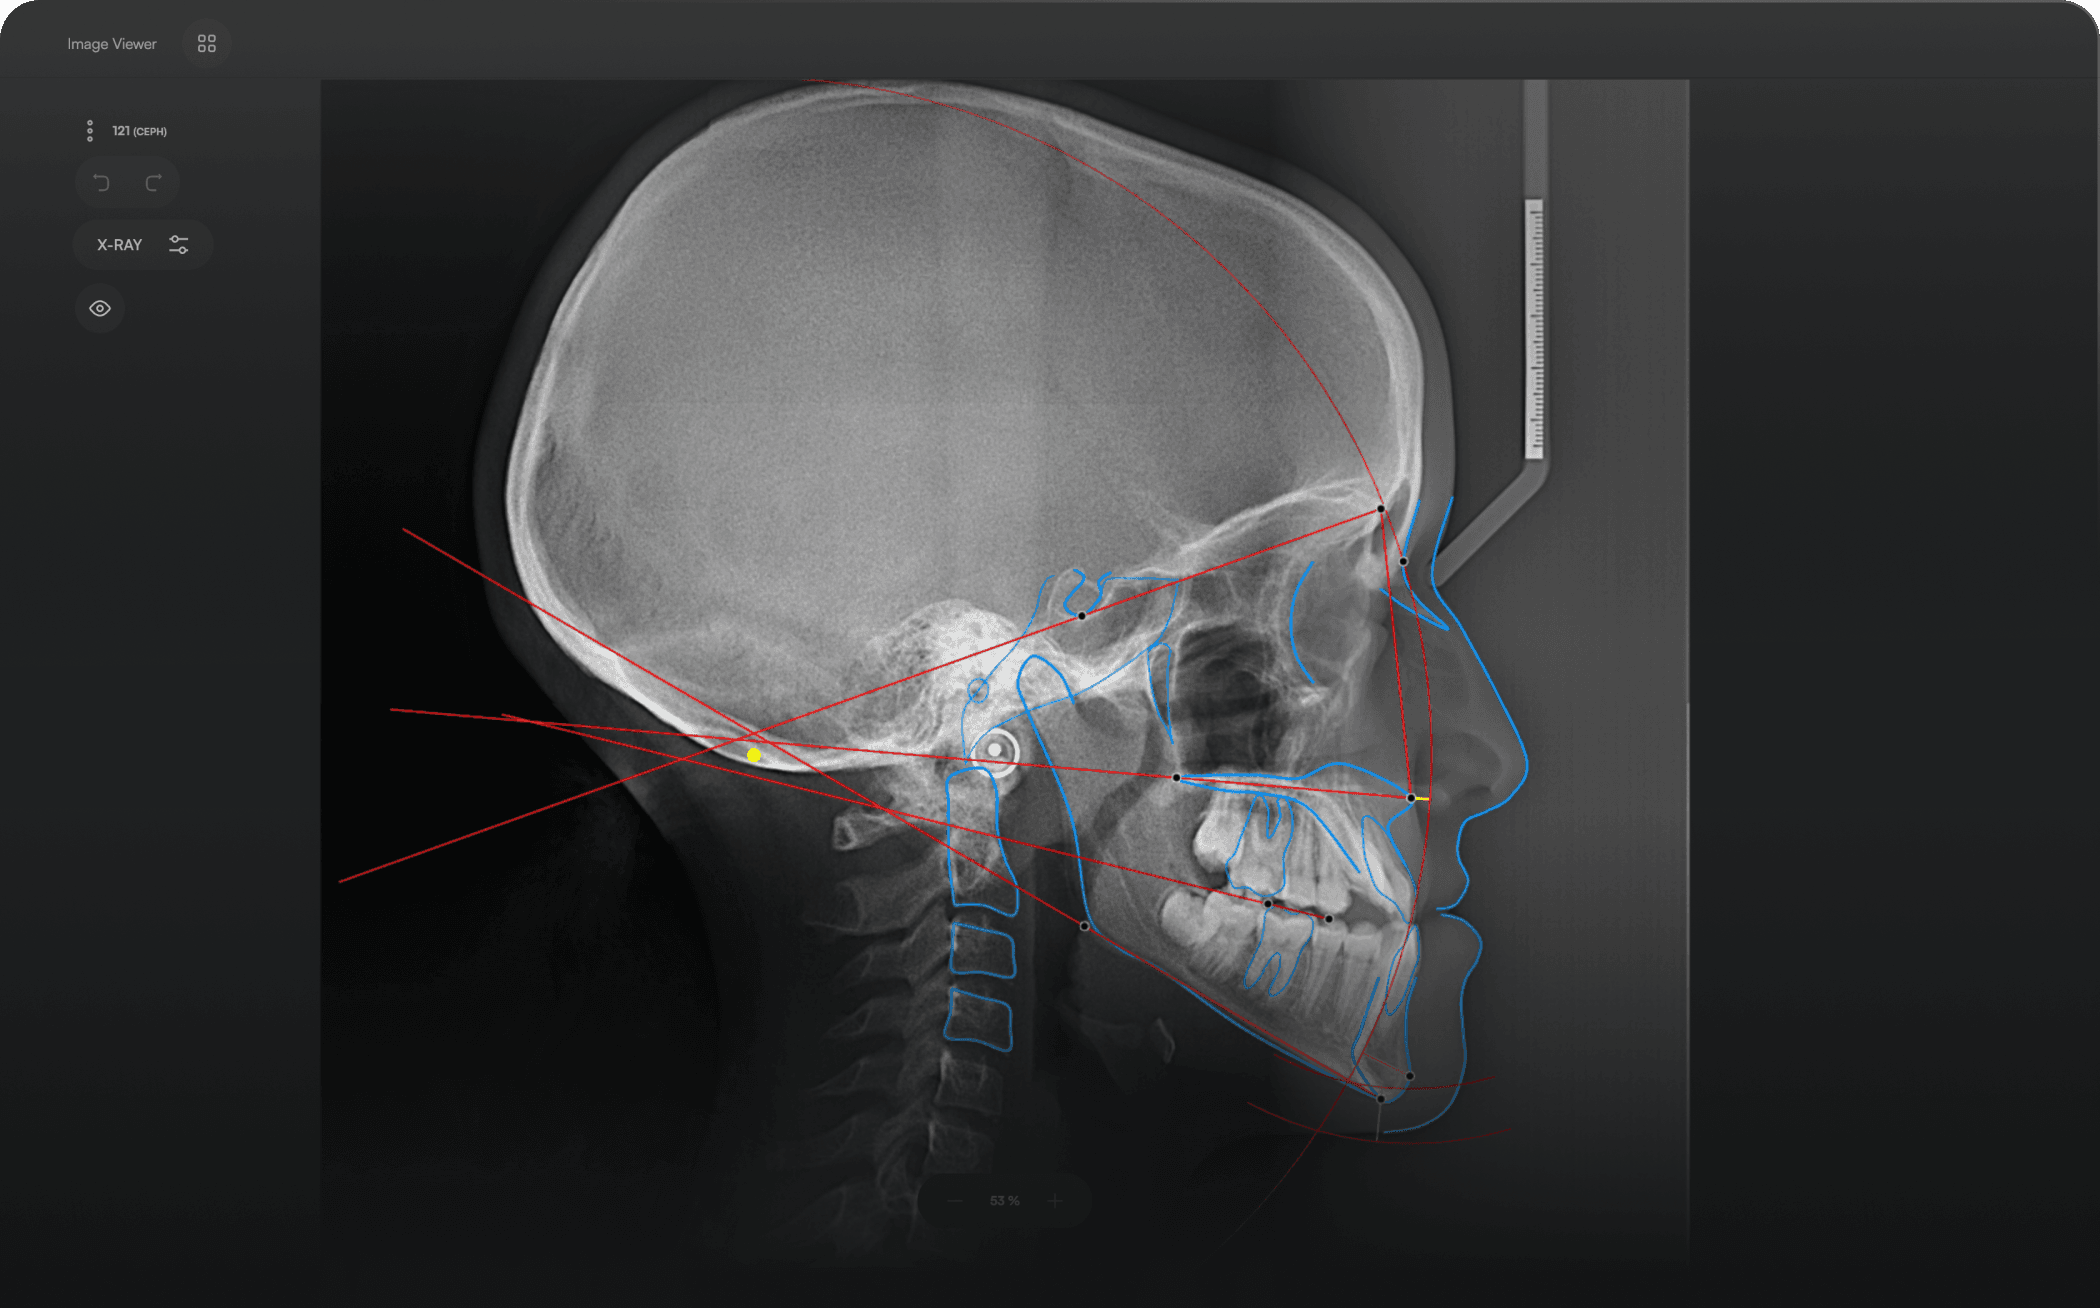

AI-driven Automated Lateral

Cephalometric Tracing

150+ landmarks traced in seconds

Automated analyses

Identify 150+ orthodontic landmarks in under 10 seconds — a task that

traditionally may take more than 30 minutes.